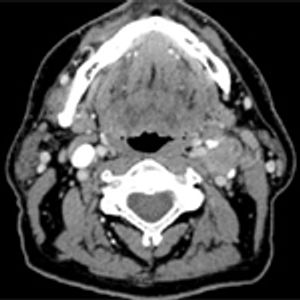

The staging of oropharyngeal squamous cell carcinoma has undergone key changes in the eighth edition of the American Joint Committee on Cancer Staging Manual, set to take effect January 1, 2018. We describe the revised staging parameters and the rationale in support of the changes.